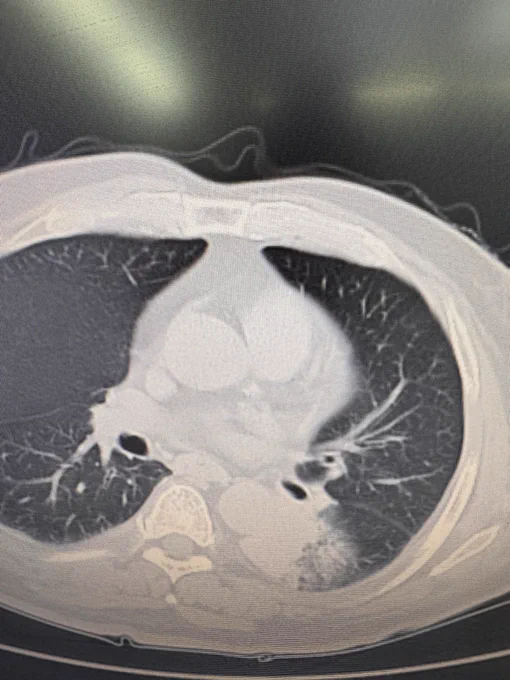

Uniportal robotic (URATS) right upper bronchial sleeve lobectomy after chemotherapy and inmunotherapy today in Wuhan

Masterclass today in Uniportal RATS at Zhongnan hospital of Wuhan University with lectures and a complex lung cancer case for live surgery: Uniportal RATS RUL sleeve lobectomy after chemotherapy and inmunotherapy. Next destination: Shenzhen

2 single port robotic lung cancer cases with Shurui today in Suzhou: Right upper lobectomy after chemotherapy and inmunotherapy and Left lower lobectomy with calcified lymph nodes